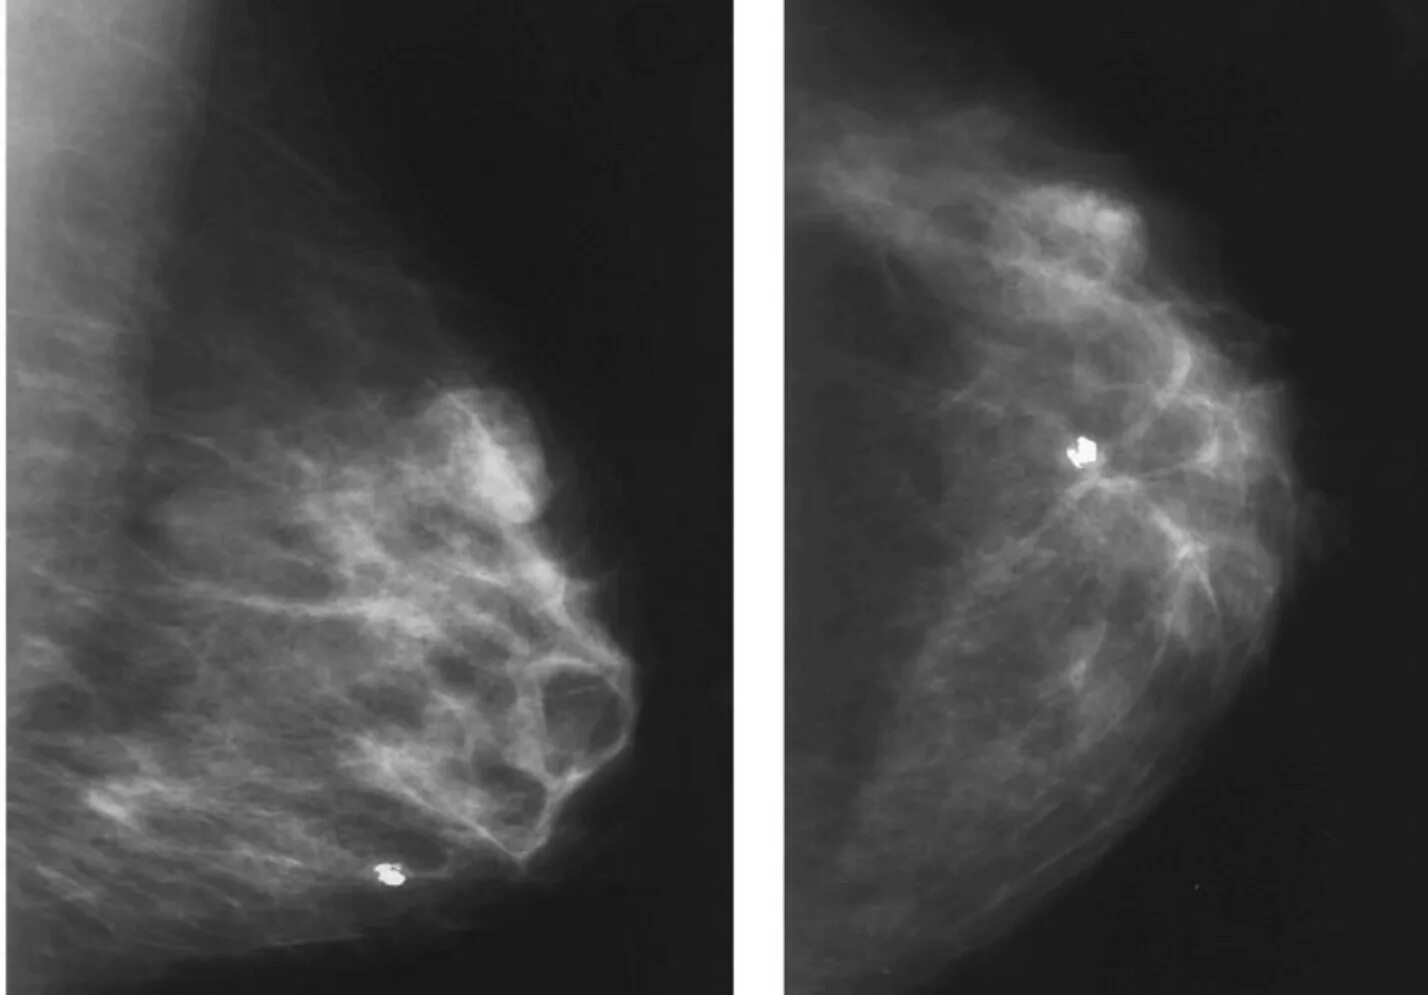

Как выглядит киста молочных желез